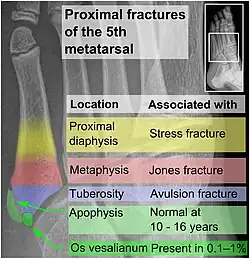

Tuberosity avulsion of the 5th metatarsal

The tuberosity avulsion fracture (also known as pseudo-Jones fracture or dancer's fracture[2] is a common fracture of the fifth metatarsal (the bone on the outside edge of the foot extending to the little toe).[3] This fracture is likely caused by the lateral band of the plantar aponeurosis (tendon).[4] Most of these fractures are treated with a hard-soled shoe or walking cast. This is needed until the pain goes away and then the patient can return to normal activities.[3] Healing is usually completed within eight weeks.[5]